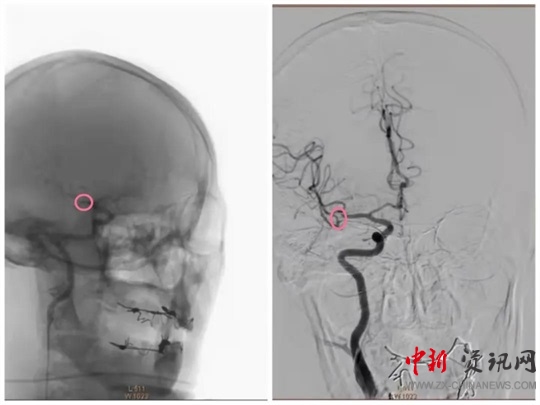

經(jīng)過一系列的術(shù)前準(zhǔn)備并經(jīng)患者家屬同意后,立即繞行病房進(jìn)入介入手術(shù)室,實(shí)施緊急手術(shù)。卒中中心團(tuán)隊(duì)、胸痛中心團(tuán)隊(duì)和介入團(tuán)隊(duì)密切配合,為患者分別實(shí)施了腦動脈造影+主動脈弓造影+顱內(nèi)動脈瘤栓塞術(shù)+冠狀動脈造影術(shù)+經(jīng)皮冠狀動脈支架植入術(shù),成功把患者從死亡邊緣拉回。目前,患者病情穩(wěn)定,各項(xiàng)指標(biāo)良好。

(動脈瘤栓塞前)

(動脈瘤栓塞后)